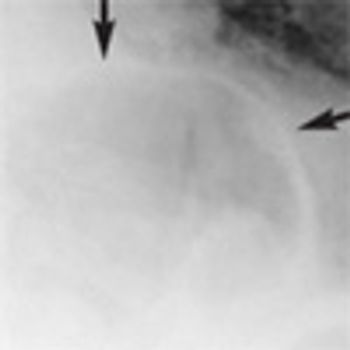

An 88-year-old woman was brought to the emergency department after she choked on a piece of meat. She had dysphagia of many years’ duration and progressive weight loss over the past 5 years.